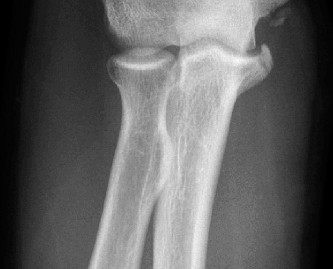

Understand common complications associated with performing surgery for scapulothoracic bursitis? CASE 33 A 42-year-old female presents to the office for follow up after sustaining a minimally displaced radial head fracture 3 months prior. She states she was initially treated in long-arm splint by the ER and did not follow up with an orthopaedic surgeon until now. Per her report, she removed the splint 4 weeks after the injury, but did not move her elbow due to pain. She now has no pain but is unable to reach that hand to her face or head. The remaining history is significant for previous ulnar nerve surgery for which she is unable to provide details. On physical examination, her upper extremity is normal except for limited flexion/extension, measured to be 80 to 50 degrees by goniometer. In addition, she has a well-healed surgical incision about the medial elbow, consistent with a previous surgery on her ulnar nerve. Her images are shown (Figs. 2–82 to 2–84).

Figure 2–82

Figure 2–83

Figure 2–84

What is the diagnosis?

- Early post-traumatic intrinsic joint contracture

- Late post-traumatic extrinsic joint contracture

- Late combined post-traumatic joint contracture

- Early combined post-traumatic joint contracture

Discussion

The correct answer is (A). Classification of post-traumatic elbow stiffness allows for better understanding of the disease and allows the clinician to treat the underlying cause of the joint contracture. Intrinsic causes include: any problem within the joint such as incongruency, loose bodies, or severe osteoarthritis. Extrinsic causes include capsular tightness, muscle contracture, heterotopic ossification, and skin contractures. Early is defined as within 6 months of the injury while late is considered to be greater than 6 months after the injury. Patients that present in the early time frame have a significantly better chance at having a good result both from nonoperative and operative treatment.